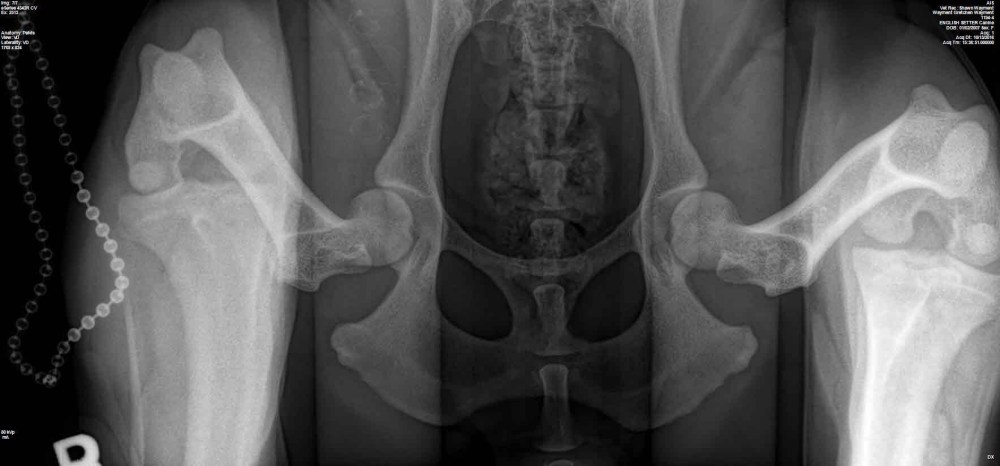

Ron Boehme, the host of the awesome Hunting Dog Podcast, asked if I ‘d contribute some veterinary specific advice to his Blog on the Hunting Dog Podcast…which I gladly accepted the challenge. Here’s the link to my latest contribution http://thehuntingdogpodcast.com/2017/04/canine-hip-dysplasia-and-pennhip/.